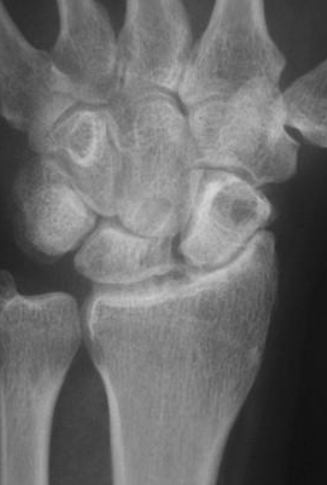

What are seen on xray for a SLAC stage 2 wrist?

PA radiograph

sclerosis

joint space narrowing- between scaphoid and entire scaphoid fossa of distal radius